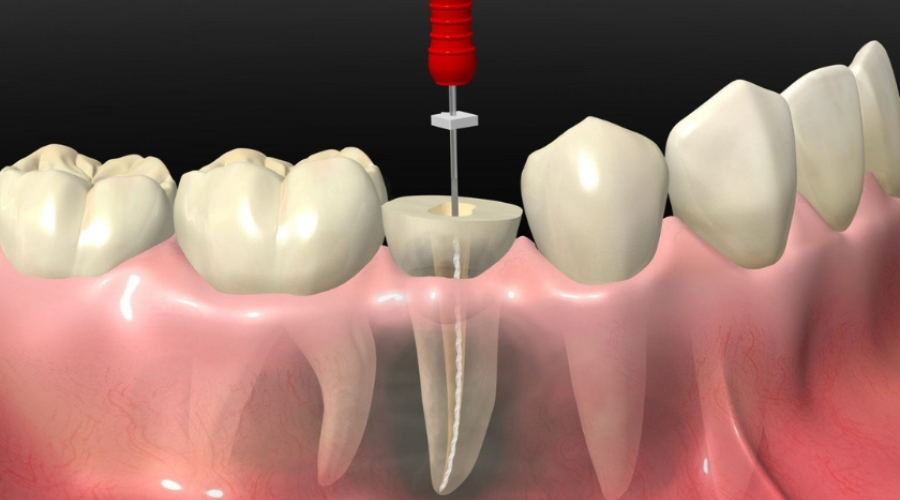

Root canal

A root canal is a dental procedure that treats infection inside a tooth by removing the infected pulp, cleaning the canals, and sealing them to prevent reinfection. It helps preserve your natural tooth, restores function, and eliminates pain. Modern techniques make the treatment safe, effective, and virtually painless.